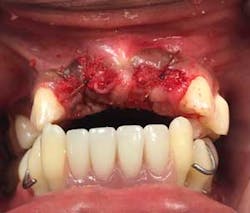

Upon returning for the above tooth removal, tooth No. 5 self-avulsed and the other teeth were removed and a temporary partial placed (figures 4 and 5).

Approximately, two-and-a-half years into active periodontal treatment and maintenance therapy, the patient and the authors discussed removal of all remaining teeth and rehabilitation of the mouth with the All-On-4 (AO4) approach (figure 6).